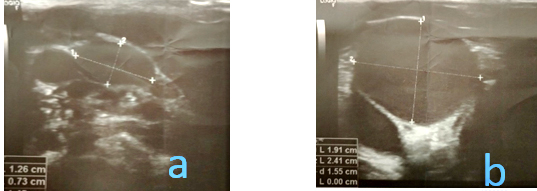

Ultrazvučni pregled mekih tkiva vrata u miru i tokom Valsalvinog

manevra prikazuje dilatiranu desnu unutrašnju jugularnu venu,

očuvanog hemodinamskog protoka.Pri Valsalvinom manevru dolazi do

dilatacije maksimalne širine lumena 24,1x19,1 mm (UZ slika 3a), u

mirovanju na poprečnom preseku širine lumena 12,6x7,3 mm (UZ slika

3b).

Slika 3: (UZ) Ultrasonografija magistralnih krvnih

sudova vrata (v. jugularis interna dex.) . Poprečni presek pri

Valsalvinom manevru (a), u miru (b)